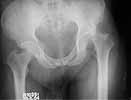

Middle aged adult hospital employee invoved in a road traffic accident. Suffered closed hip dislocation left side and fracture both bones right forearm(ulna compound) Underwent closed reduction of right hip and debridement with ORIF of forearm. Pre op X-ray showed acetabular rim fracture and post op X-ray showed a suspicious fracture line through the head of femur. One fragment of acetabulum seen displaced. CT done subsequently shows an undisplaced fracture through the head of femur with the acetabular rim fracture which is displaced.

The femoral head fracture in Dr. George's (unknown age or medical conditions) male patient is essentially nondisplaced, the hip joint is congruent, there is no joint debris, and the wall is peripheral. Leave it alone.